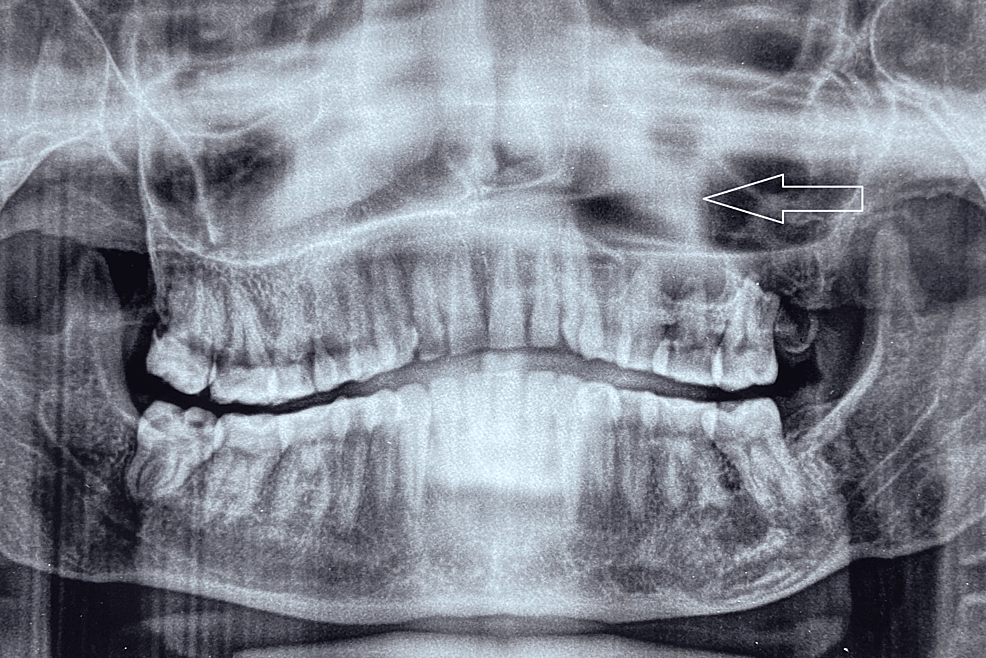

Maxillary Odontogenic Keratocyst . — the odontogenic keratocyst (okc) is one of the most aggressive odontogenic cysts. odontogenic keratocysts (okc), previously known as keratocystic odontogenic tumors (kcot or kot), are rare benign cystic lesions involving the mandible or. The main difference between okcs and other jaw cysts. — an odontogenic keratocyst (okc) is a benign but aggressive intraosseous tumor derived from the. — odontogenic keratocysts (okcs), first described by philipsen in 1956 [1], are benign intraosseous lesions of. figure 5 odontogenic keratocyst between roots of right maxillary incisors (circled by white dots). — odontogenic keratocysts (okc), previously known as keratocystic odontogenic tumours (kcot or kot), are. — the odontogenic keratocyst (okc) is one of the most aggressive odontogenic cysts.

— odontogenic keratocysts (okcs), first described by philipsen in 1956 [1], are benign intraosseous lesions of. figure 5 odontogenic keratocyst between roots of right maxillary incisors (circled by white dots). The main difference between okcs and other jaw cysts. — an odontogenic keratocyst (okc) is a benign but aggressive intraosseous tumor derived from the. odontogenic keratocysts (okc), previously known as keratocystic odontogenic tumors (kcot or kot), are rare benign cystic lesions involving the mandible or. — the odontogenic keratocyst (okc) is one of the most aggressive odontogenic cysts. — odontogenic keratocysts (okc), previously known as keratocystic odontogenic tumours (kcot or kot), are. — the odontogenic keratocyst (okc) is one of the most aggressive odontogenic cysts.

Maxillary Odontogenic Keratocyst The main difference between okcs and other jaw cysts. — an odontogenic keratocyst (okc) is a benign but aggressive intraosseous tumor derived from the. The main difference between okcs and other jaw cysts. — odontogenic keratocysts (okc), previously known as keratocystic odontogenic tumours (kcot or kot), are. — the odontogenic keratocyst (okc) is one of the most aggressive odontogenic cysts. — the odontogenic keratocyst (okc) is one of the most aggressive odontogenic cysts. — odontogenic keratocysts (okcs), first described by philipsen in 1956 [1], are benign intraosseous lesions of. odontogenic keratocysts (okc), previously known as keratocystic odontogenic tumors (kcot or kot), are rare benign cystic lesions involving the mandible or. figure 5 odontogenic keratocyst between roots of right maxillary incisors (circled by white dots).